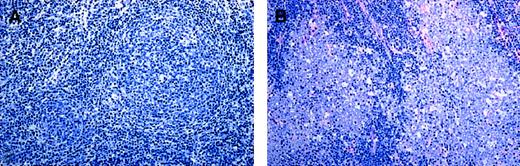

On the basis of the number of blasts in 10 unselected HPFs and in keeping with the recommendations of the new WHO classification,1 29 lymphomas were classified as grade 1 (FL 1), 33 as grade 2 (FL 2), 15 as grade 3 (FL 3), and 12 as grade 3 with DLBL (FL 3 + DLBL). In all cases a follicular growth pattern was observed in at least 25% of the area infiltrated. The cytologic composition of FL 3, however, was heterogeneous. Among FL grade 3, 11 tumors consisting of centroblasts and centrocytes were designated as FL 3a. In these cases, centrocytes were often large, and the distinction between large centrocytes and small centroblasts was not always clear-cut (Figure 1A). Four FL grade 3 tumors were exclusively composed of large and small blasts, without residual centrocytes. These were classified as FL 3b (Figure 1B). All FL 3 tumors with a DLBL component consisted of (large or small) blasts exclusively and were, therefore, designated as FL 3b + DLBL. In these cases, no clear-cut evidence was obtained for follicular colonization or partial follicular involvement of pre-existing germinal centers by DLBL. Based on these findings, the cases were stratified into 2 groups, depending on the presence of centrocytes: group A consisted of FL with preserved maturation to centrocytes (FL 1, 2, and 3a), and group B comprised all cases without centrocytes (FL 3b and FL 3b + DLBL).

Cytomorphologic features of FL 3.

(A) FL 3a. Neoplastic infiltrate is composed of large noncleaved cells (centroblasts) and small to medium-sized, sometimes large, cleaved cells (centrocytes). (B) FL 3b. A population of small and large noncleaved cells (centroblasts) is seen, without an admixture of centrocytes. Original magnification, × 800. Stained with Giemsa.

In group A the neoplastic follicles were poorly demarcated and seemed to merge with the interfollicular infiltrate, while follicles in group B lymphomas were often sharply demarcated from the surrounding interfollicular area (Figure 2A-B). Most cases of FL 3a (7 of 11), in spite of their high average content of centroblasts, contained some follicles with fewer than 15 blasts per HPF (usually between 5 and 15).

Structural features of FL 3.

(A) FL 3a. Note that the neoplastic follicular infiltrates are poorly demarcated to the surrounding interfollicular zone and seem to merge with the T-cell area. (B) In contrast, in FL 3b, follicles are sharply demarcated, and there is no merging with the interfollicular infiltrate. Original magnification, × 150. Stained with Giemsa.